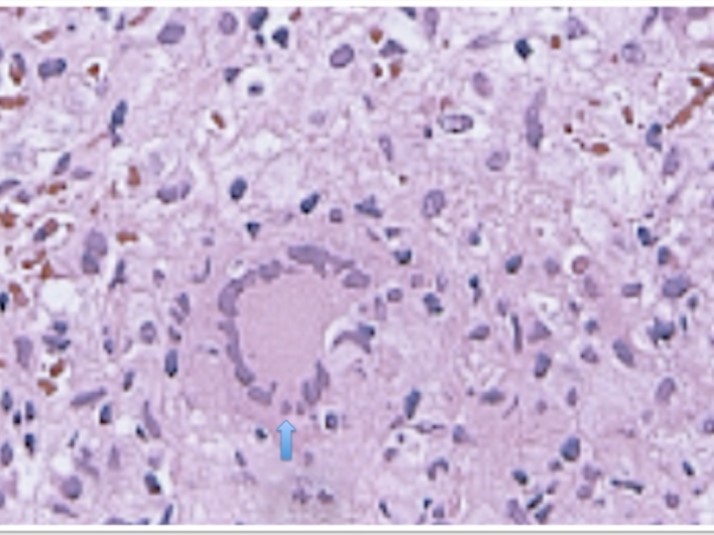

Laboratory analysis showed hemoglobin, 10.9 g/dL; white blood cell count, 9,800 cells/mm3, serum albumin, serum total bilirubin, alanine aminotransferase, aspartate aminotransferase, prothrombin time, hepatitis B surface antigen, and antibodies to hepatitis C, serum alpha-fetoprotein (AFP), carcinoembryonic antigen and carbohydrate antigen 19-9 (CA 19-9) were within normal range. Blood cultures were negative. Chest x-ray was normal. Ultrasound of abdomen showed a 10 cm hypoechogenic lesion in left liver (Figure 1). An abdominal CT showed a well-defined heterogeneous mass situated in his left hepatic lobe measuring 10 cm × 7 cm (Figure 2, Figure 3). The lesion featured central necrosis, a hyper-dense rim and a mild enrichment from the arterial phase in the CT, The diagnosis of primary hepatic tumor was suspected. An ultrasonography-guided needle biopsy of the liver was scheduled in order to rule out malignancy and to have a complete diagnosis. Cytology demonstrated a tuberculosis granuloma, acid-fast bacilli culture was positive (Figure 4). Anti-tuberculous therapy including isoniazid, rifampin, ethambutol, and pyrazinamide were prescribed. The patient completed the 6-month course of medication with success. The patient’s appetite and body weight were restored to previous levels. One year after the completion of treatment, the patient remained completely asymptomatic with disease free.

Figure 4.Hepatic histopathology of patient showing granuloma

CT-guided aspiration and biopsy can confirm the diagnosis. Percutaneous needle biopsy of the liver using ultrasound, CT has greater than 90 percent sensitivity. In case of pseudotumor tuberculosis mimicking a carcinoma, the role of biopsy is important because it can change therapeutic attitudes. The definitive diagnosis of this disease is conventionally made by histological analysis of caseating granuloma or demonstration of acid-fast bacilli on culture of biopsy specimen 13.